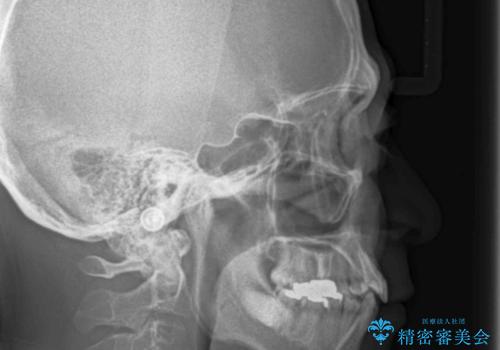

患者様の「できるだけ短期間で治療を終わらせたい、セラミックが入れられたら良いので大がかりなことはしたくない」とのご要望により、3Dシミュレーションを何度も行い患者様とのコンサルを重ね、上顎左右犬歯と左下2を抜歯して②のプランである補綴前矯正(インビザライン)を行うことにしました。

小臼歯の歯根長が長いことを治療前にレントゲンで確認し抜歯部位を決定しました。